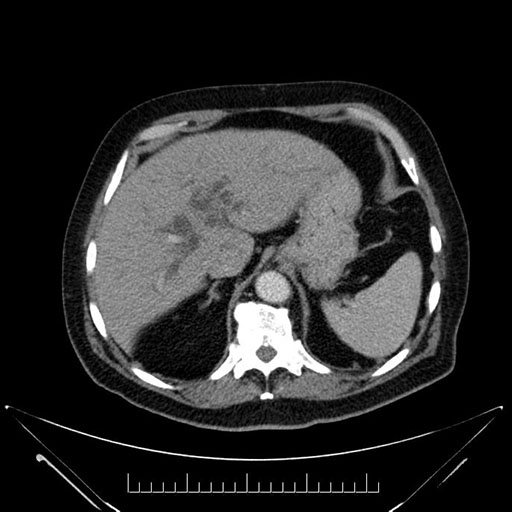

Axial - 3 months prior